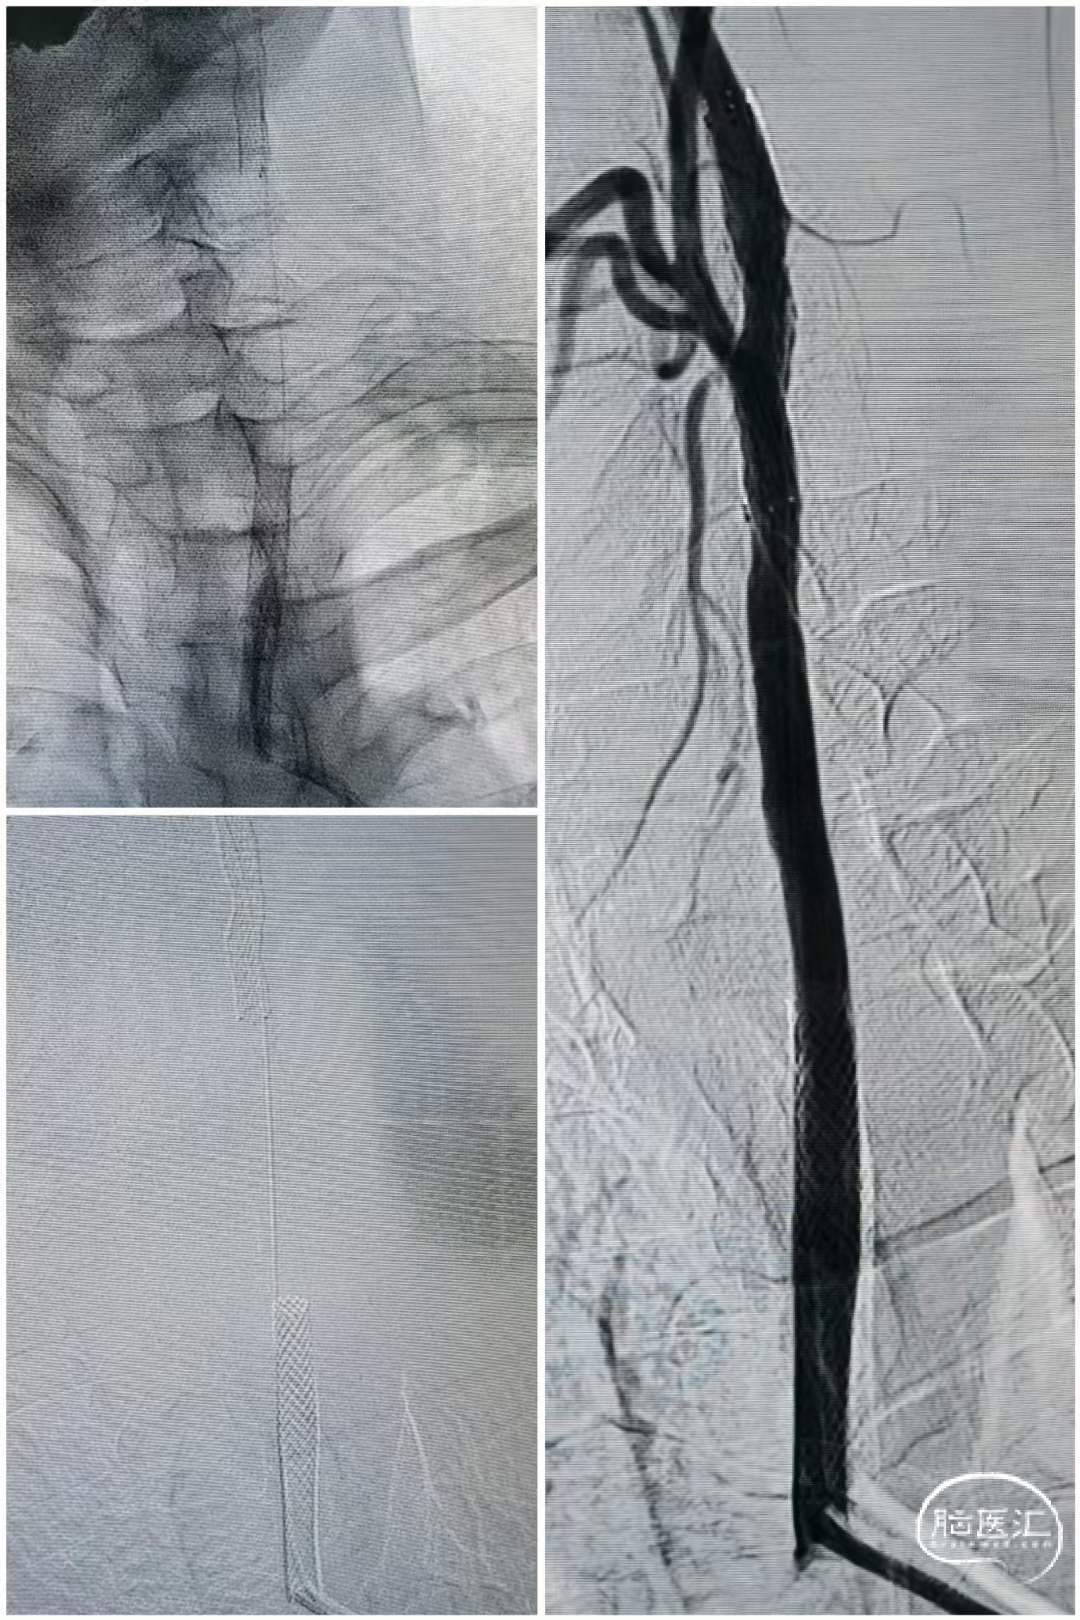

术后造影

造影可见:双侧病变改善,患者症状好转安返病房。